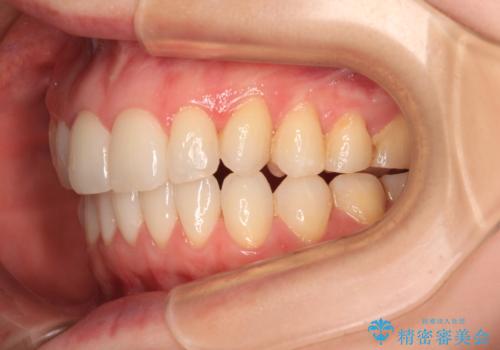

- 前歯のデコボコや八重歯の様になっていることを気にして来院された患者様です。

犬歯捻れて前方に飛び出しており、下顎前歯もそれに沿うようにデコボコとなっていました。

IPR(歯と歯の間を削る処置)によりスペースを獲得して上下顎前歯のデコボコを改善し、前歯が前方に突出しないように設定した上で、インビザラインにて矯正治療を行うこととしました。

途中体調を崩され、長い期間矯正治療を休むことになったため4年半ほどの治療期間がかかりました。